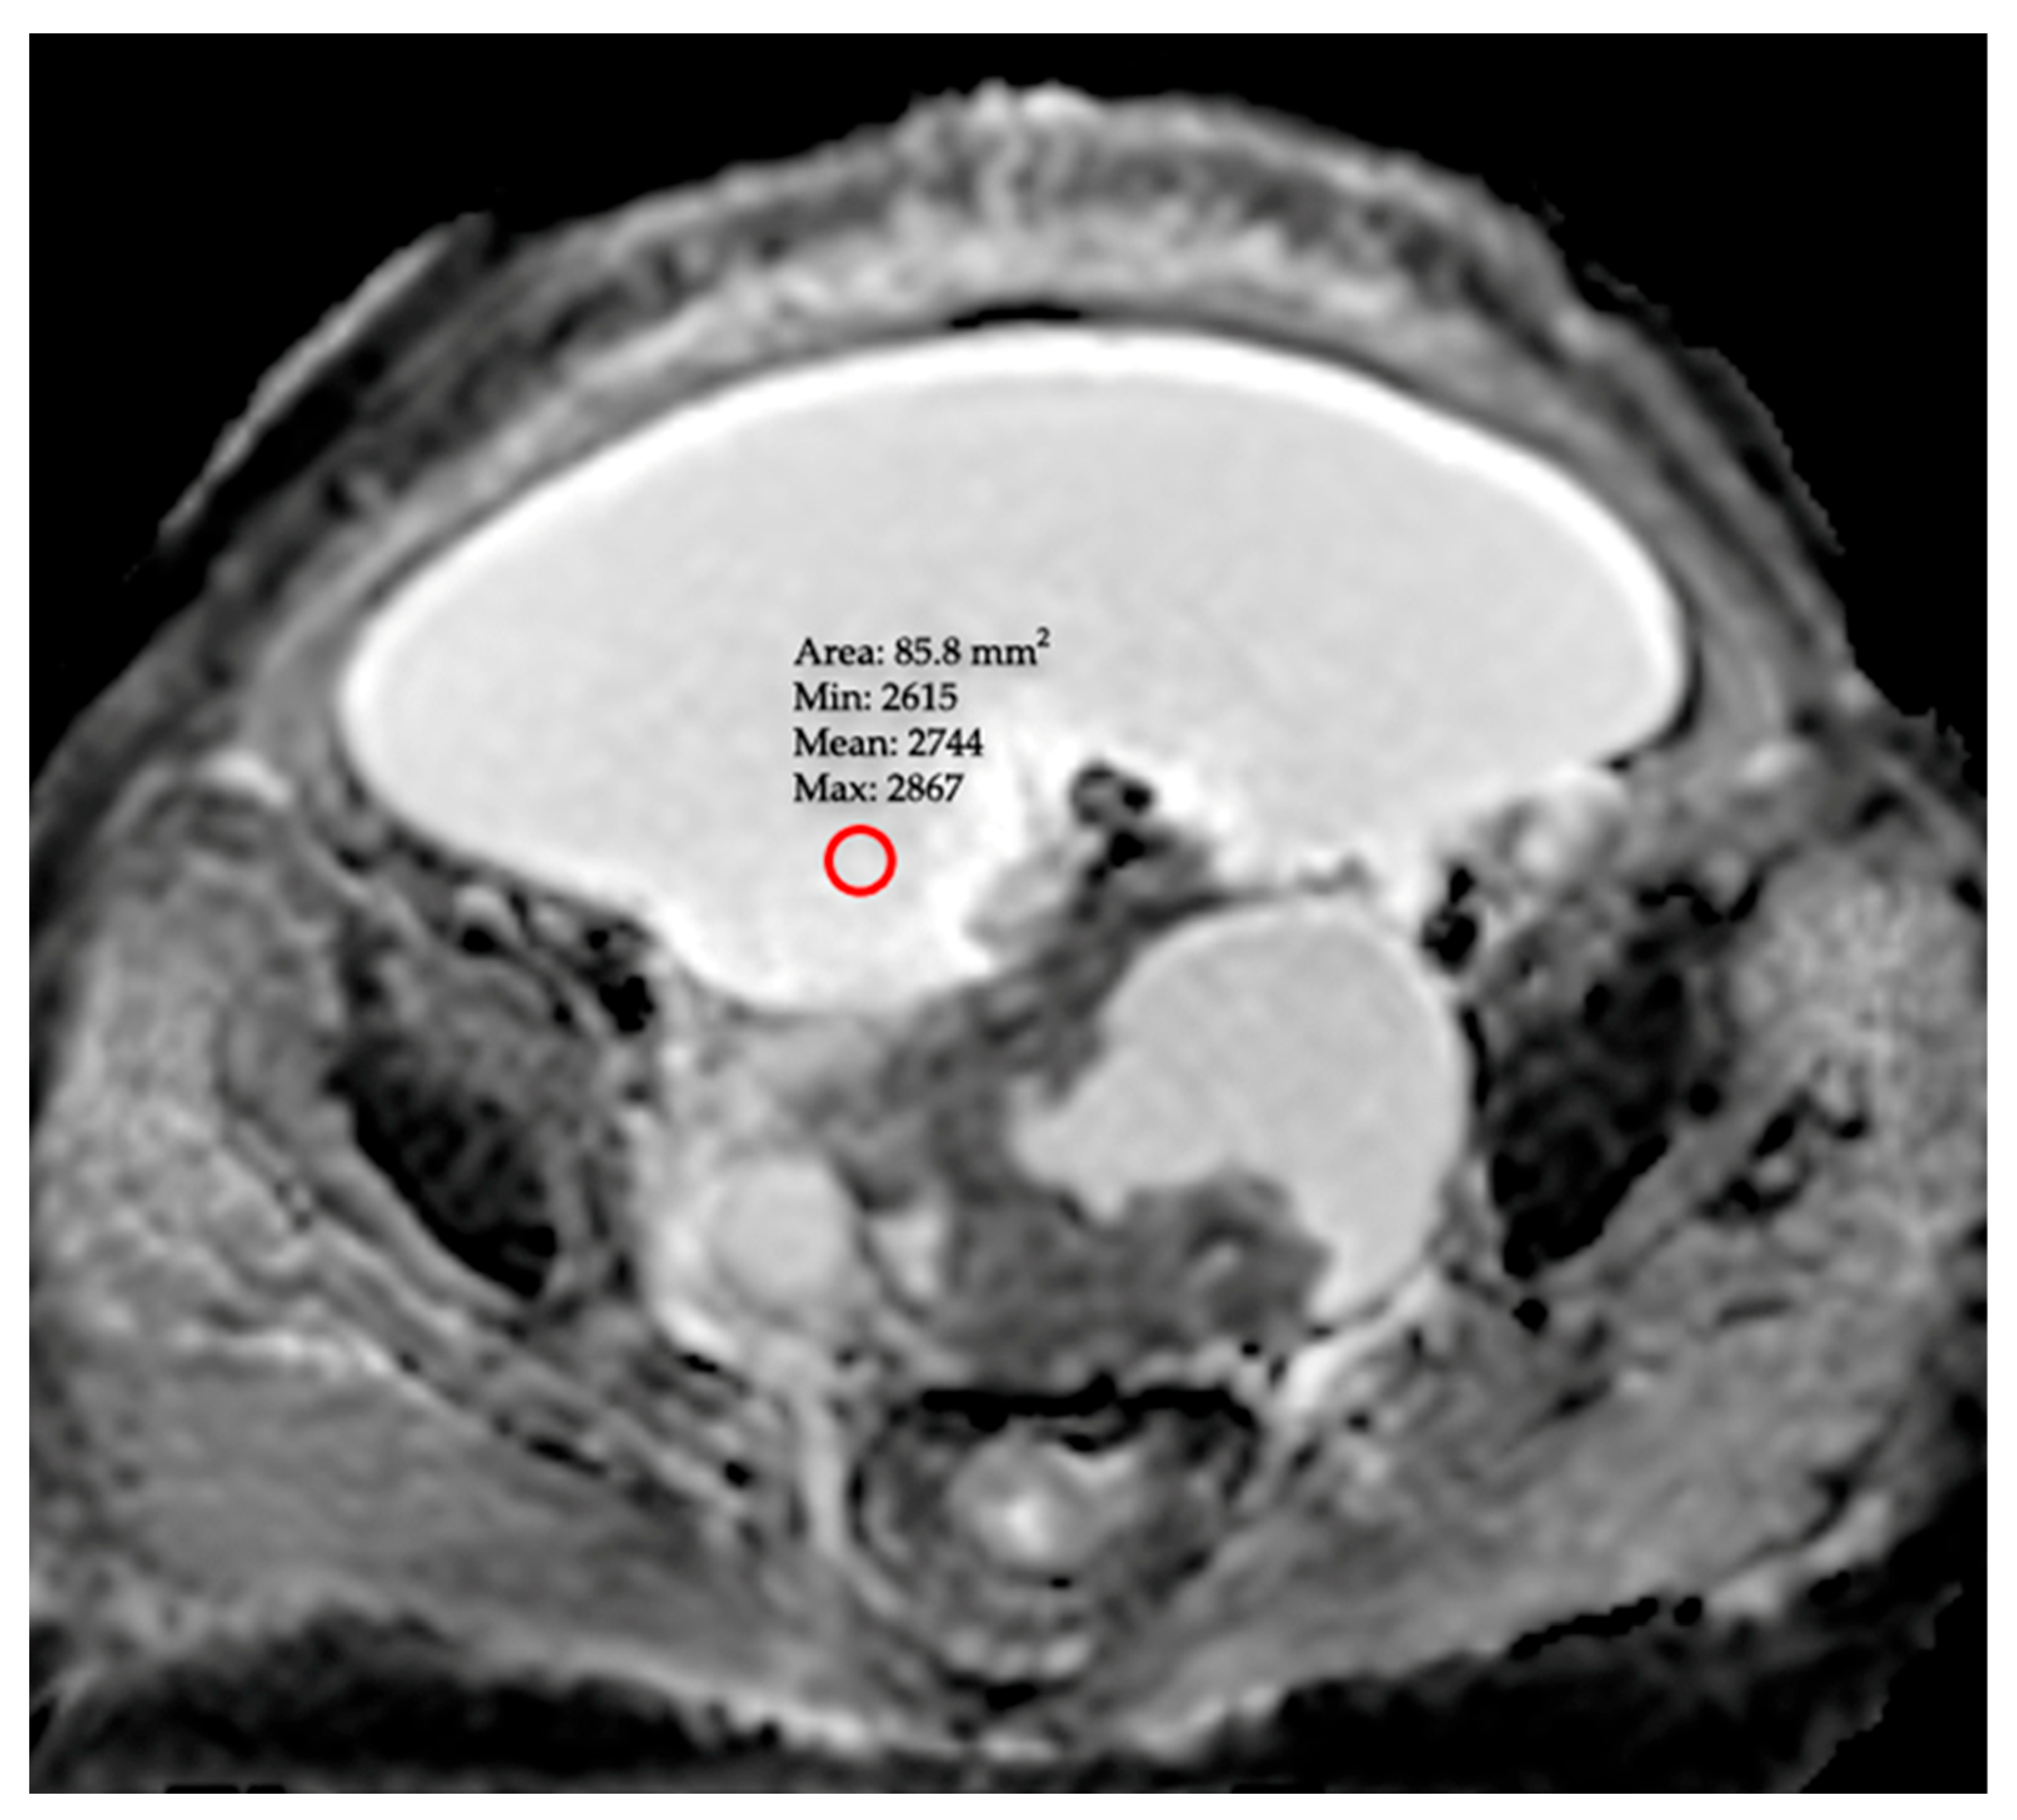

- ADCmin (Minimum ADC): A value obtained from a single ROI placed on the area exhibiting the lowest signal intensity (appearing darkest) on the ADC map, following a meticulous inspection of the entire peritoneal cavity. To prevent this measurement from being subjective, observers used standard window settings (window width/level). This approach is predicated on the hypothesis that it may reflect the most aggressive component of the pathology by specifically targeting the region of highest focal malignancy or greatest fluid viscosity.